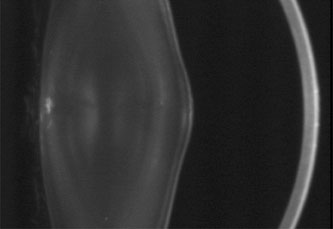

Fig. 6. Christmas-tree cataract. Multiple small, irregularly sized opacities in the superior and posterior superficial cortex in a 43-year-old male patient with DM (Scheimpflug image).

Fig. 7. Christmas-tree cataract. Dust- and flake-like iridescent and highly refractile multicolored “needles” crisscross the anterior lens cortex in a patient with DM.